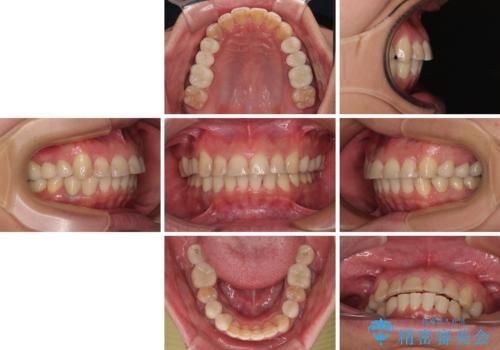

矯正治療にやや時間がかかりましたが、歯列はきれいに整い、気になっていたむし歯や銀歯は自然な色合いに仕上がりました。